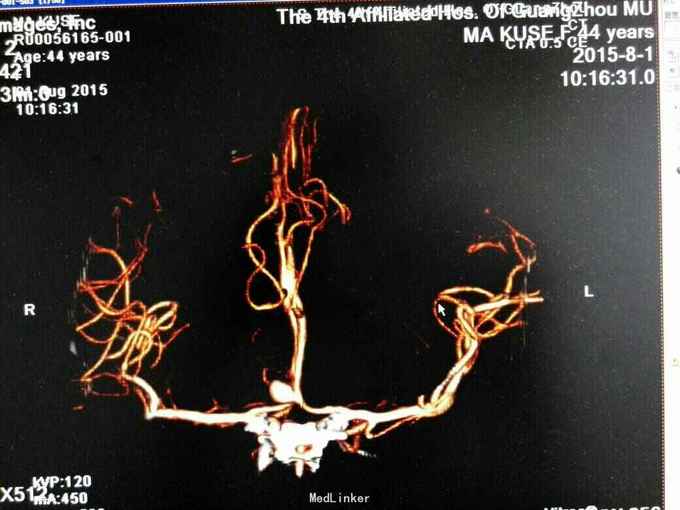

昏迷状态,GCS为5分,双侧瞳孔等大等圆,直径约等于3.0mm,对光反射迟钝,颈抵抗,痛剌激双下肢过伸,双侧巴氏征(+),入院当天头颅CT:广泛蛛网膜下腔出血,脑肿胀,侧脑室、三、四脑室出血并铸形,CTA及DSA:前交通动脉瘤。入院后第八天头颅CT:弥漫性脑肿胀脑疝。

诊断:1.前交通动脉瘤破裂出血(Hunt-Hess分级为4级),2全脑室系统出血并铸形。入院后予抗感染、脱水及扩血管治疗,并行双侧侧脑室钻孔引流术,气管切开术,脑血管造影及动脉瘤栓塞术,病情一度相对平稳,转为浅昏迷,GCS为8分,入院第八天突发出现双侧瞳孔散大,查头颅CT提示“脑肿涨脑疝”,即行扩大冠状切口双额颞去骨瓣减压术,术后双侧瞳孔回缩,行脱水、扩血管、康复等治疗。